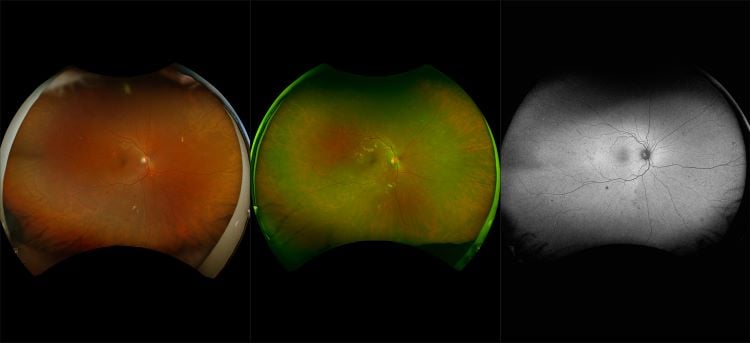

optomap Multimodal Diabetic Eye Disease Cases

Optos offers multimodal imaging with all ultra-widefield devices. Having both ultra-widefield and four images captured in less than one second has been shown to enhance pathology detection and disease management as well as improve practice and clinic flow. Ultra-widefield multimodal imaging is important across all access points of patient care - screening, detection, diagnosis, and treatment.